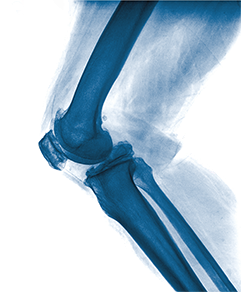

Специализируется на лечении последствий спортивных травм, плечевого и коленного суставов. Имеет большой опыт эндопротезирования коленного и тазобедренного суставов.

- повреждения менисков;

- различные травмы колена и бедра;

- артроскопия;

- повреждения внутри коленного или других суставов;

- проблемы с коленными связками;